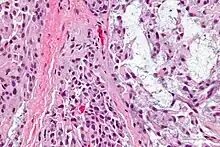

Myoepithelioma, here with plasma cell-like myoepithelial cell.